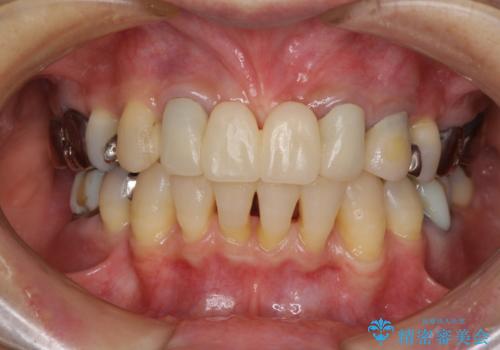

- 矯正治療を行った歯科医院で装着した前歯の仮歯が不快とのことで来院された患者様です。

仮歯自体はとても綺麗でしたが、2本の歯が欠損している部分に上唇小帯が入り込んでいたため、歯肉形成を行った上で仮歯を調整し、オールセラミックブリッジを装着することとしました。

他にも治療が必要な歯があったため、合わせてセラミッククラウンやセラミックインレーで治療することとしました。

上唇小帯を切除したことで、ブリッジのダミー部分に触れて腫れていた歯肉は健全な状態になりました。

隙間もなくなったことで話す際の空気の漏れや、ものが挟まることもなくなりました。